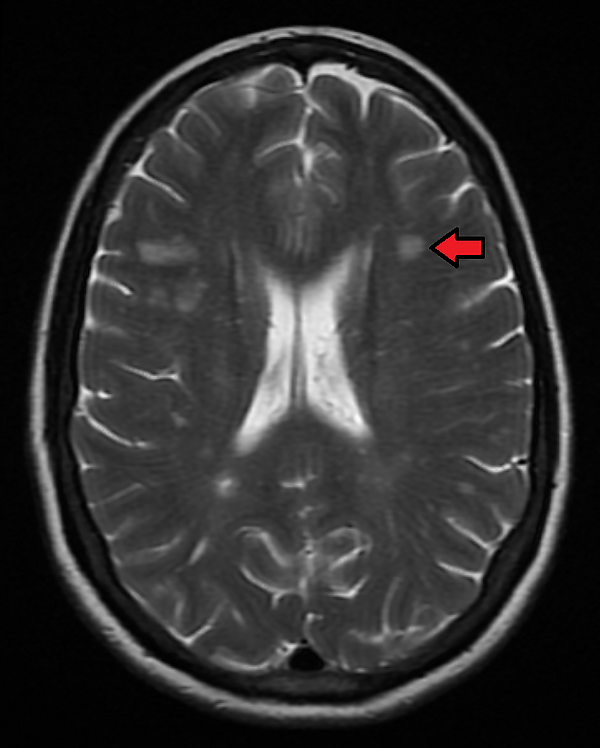

- компьютерную, магнитно-резонансную томографию головного мозга, спинного мозга и периферических нервов[6][7] — на начальных стадиях в половине случаев изменения на томограммах головного мозга не выявляются, на томограммах спинного мозга выявляются поражения более 3 грудных, поясничных сегментов или конус спинного мозга[11];